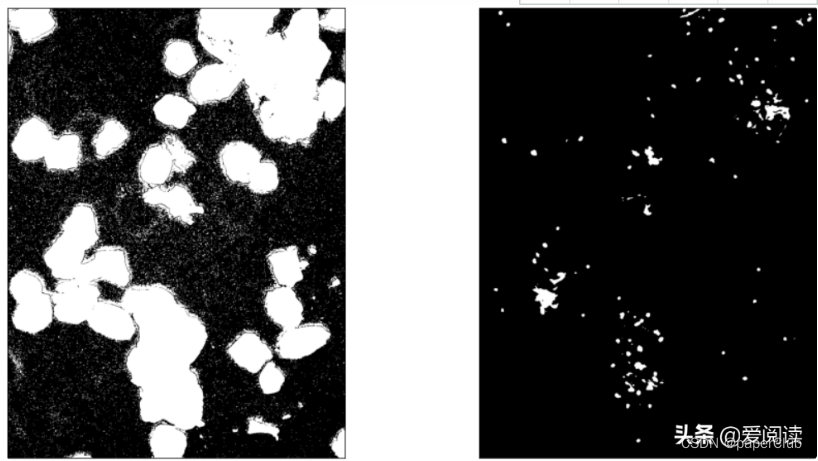

最终细胞核分割定位效果:左边是原图,右边是细胞核行为结果:

例子1:

例子2:

可以看到效果很得不错的。当然这里面还有很大的优化空间。

2.细胞核分割方法2: